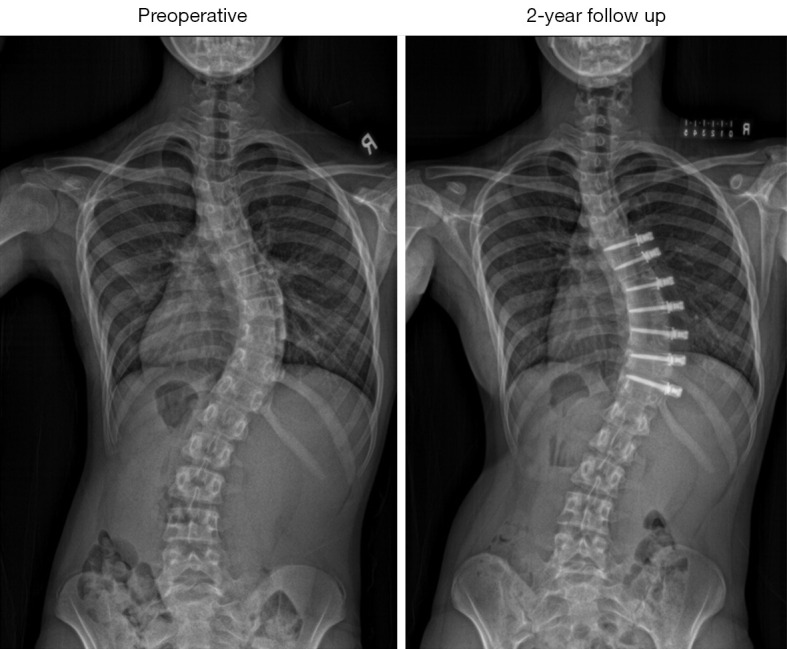

Background: Vertebral body tethering (VBT) has shown improvements in coronal and sagittal plane correction in adolescent idiopathic scoliosis (AIS) patients, but axial correction over time remains unexplored. Three-dimensional (3D) spine reconstruction was used to analyse correctional changes in all spinal planes post VBT surgery.

Case description: AIS subjects who underwent thoracic VBT surgery with a minimum 2-year follow-up were assessed. Biplanar radiographs were used for 3D spinal reconstructions, 3D coronal, sagittal thoracic kyphosis (TK), lumbar lordosis (LL), and axial rotation measurements were compared at pre-operative (pre-op), immediate post-operative (post-op), 1-year, and 2-year follow-up. Eight patients (7 females, 1 male) with a mean age of 11.8±1.3 years with right thoracic curves (mean 50.4°±8.1°) were followed for 26.8±4.1 months. Mean coronal Cobb angle showed significant improvement: 28.4°, 19.2°, and 27.1° at post-op, 1-year, and 2-year follow-up (P<0.001). Minimal changes were seen in sagittal plane: TK-35.2°, 39.0°, 31.3°, 37.0°; LL-46.1°, 42.8°, 36.5°, 42.8° (pre-op, post-op, 1-year, 2-year) respectively. Apical axial rotation improved from -5.5°±5.0° to -1.4°±4.8° post-op, then deteriorated to -3.2°±4.9° at 1 year and -7.0°±5.9° at 2 years, with no significant changes.

Conclusions: This is the first case series to use 3D radiographic digital measurements to reveal apical axial rotation progression in thoracic curves despite improved coronal curvature. While larger scales studies with longer follow-up are needed to verify our findings, surgeons and patients should be aware of such findings in their decision to select VBT as their procedure of choice.